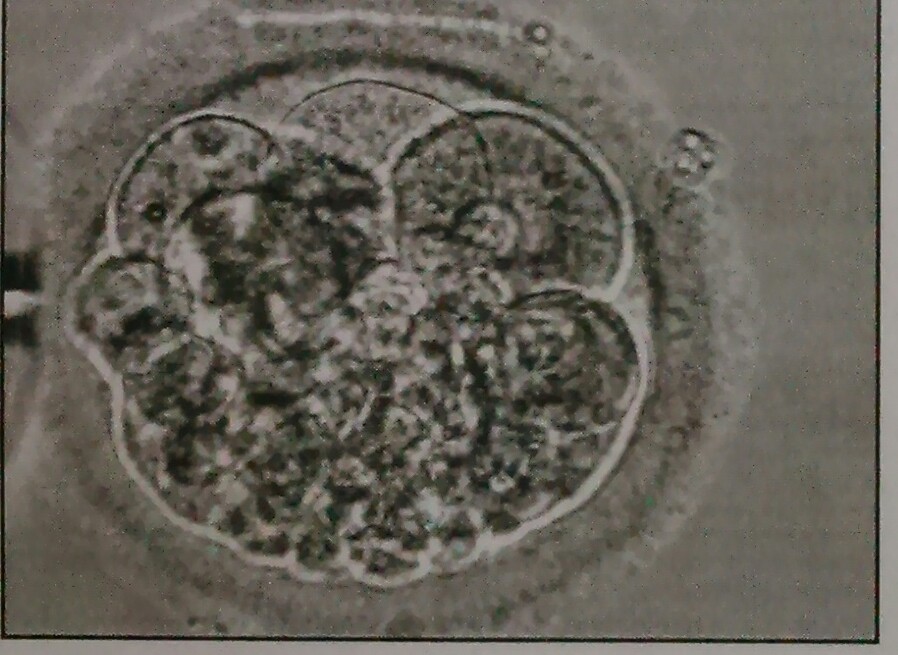

soweit ich es von dem Bild erkennen kann, sehe ich einen 6-Zeller mit relativ gleichmäßigen Unterzellen und einem Anteil an Fragmenten von ca 30%. Die Gesamtqualität würde ich mit gut bis mittel angeben, wobei ich darauf hinweisen möchte, dass so eine Momentaufnahme nur eine sehr begrenzt aussagekräftige Beurteilung zulässt.

Können sie mir sagen, um welche Qualität es sich hierbei handelt?

Mir wurde nur gesagt, 6-8 zeller und sieht gut aus.